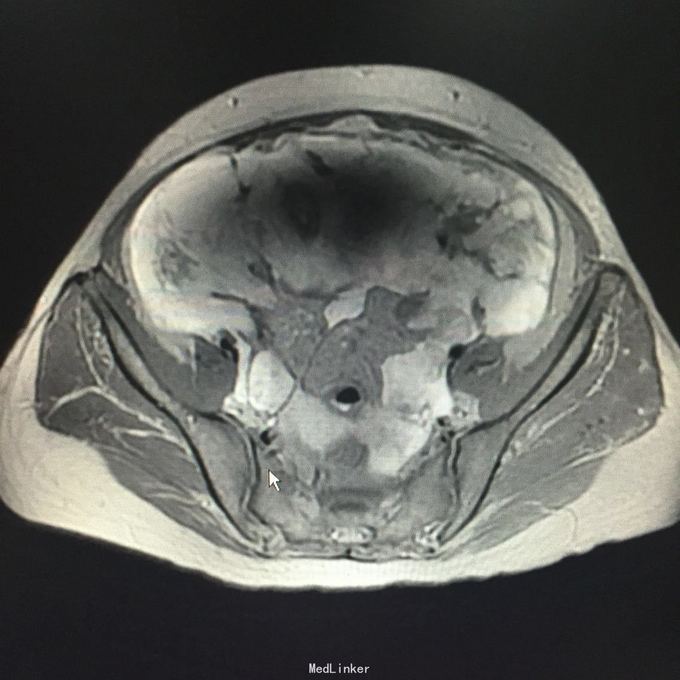

查体:腹围93cm,腹部膨隆,腹肌紧张,全腹部可扪及实性占位,移动性浊音可疑阳性。入院查CA125 472U/ml,HE4 609pmol/l,行B超引导下腹腔穿刺,抽出腹水1000ml,腹水病理:癌细胞。行全腹MR:道格拉斯窝占位性病变,考虑为恶性肿瘤(左侧附件来源),并大网膜、肠系膜、腹膜广泛转移,腹腔大量积液,肝S7/8段包膜下异常灌注灶。

入院诊断:盆腹腔肿物。行剖腹探查术,术中见,腹腔积血500ml,全腹及盆腔簇集状分布大量烂肉样赘生物,腹膜厚,表面密集分布肿瘤组织,子宫及双附件封闭,未探及,考虑手术出血风险大,与患者家属沟通后,暂予以行姑息治疗,遂予以行腹式盆腹腔肿物部分切除术,术中出血1000ml。术后病理:符合癌肉瘤,结合临床发病部位,考虑为卵巢恶性苗勒氏管混合瘤。术后诊断:卵巢恶性苗勒氏管混合瘤IV期。